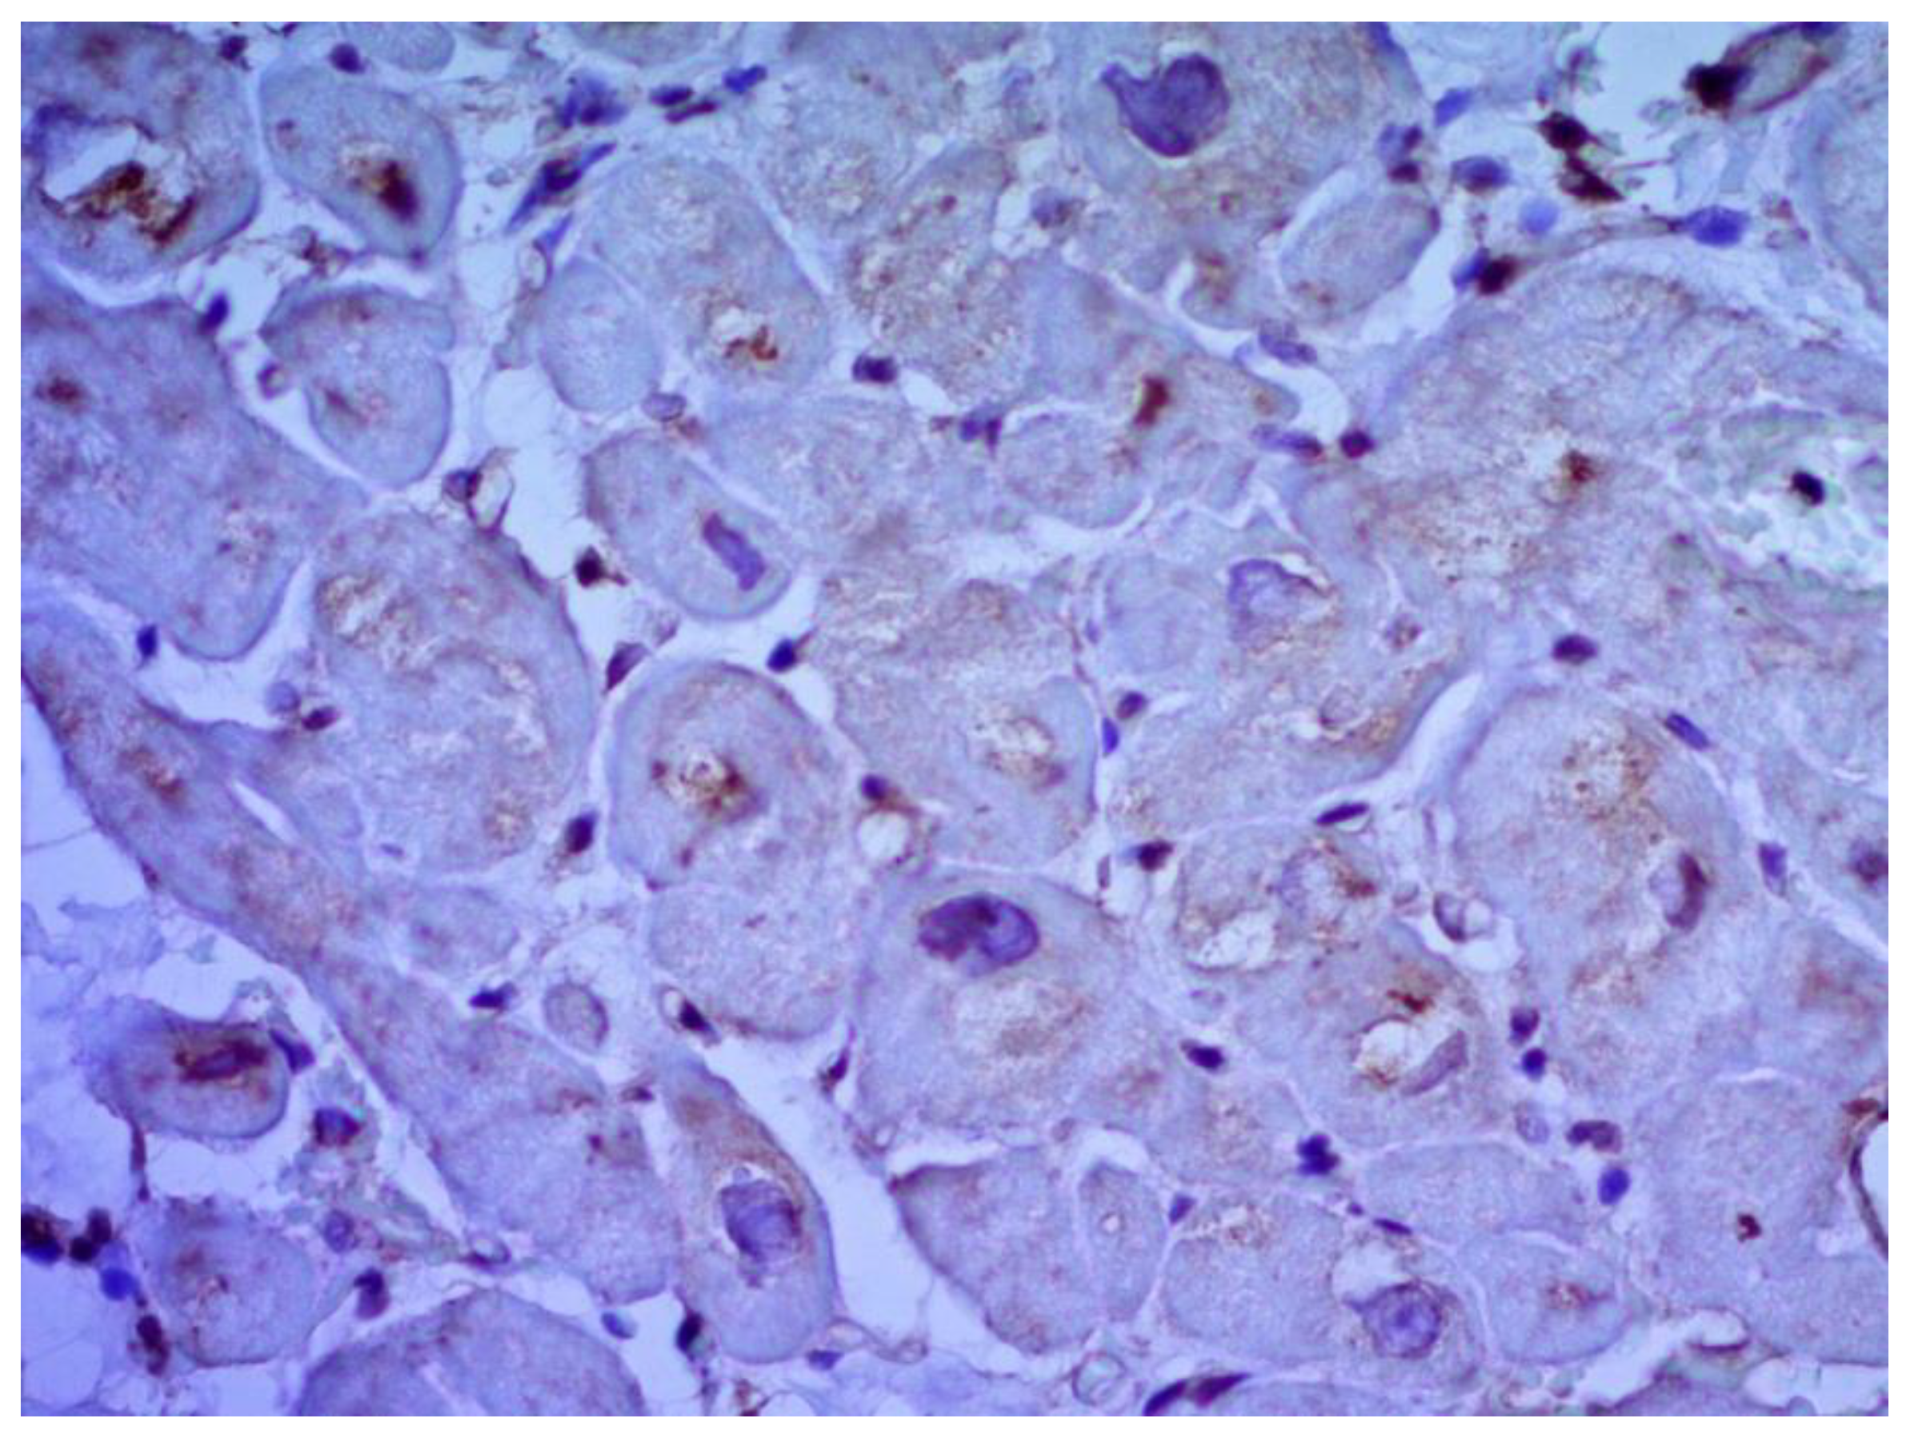

Figure 4. Endomyocardial infiltration with CD3+ lymphocytes. Immunohistochemical study, antibodies to the Epstein-Barr virus, ×200.

Inflammatory changes in the myocardium were detected in 32 patients (47.8%), including nine patients (28.1%) with lymphocytic infiltration of less than 14 lymphocytes per mm2 (Figure 4 and Figure 5). The data obtained with EMB from RV and IAS were comparable. Inflammatory changes in RV correspond to a similar finding in IAS, while fibrotic changes in RV correspond to the same evidence in IAS. According to the results of immunohistochemical analysis, the virus expression was detected in one of these patients (3.1%). A combination of human herpes simplex virus type 2 and Epstein-Barr was found. No virus expression was detected in the remaining patients.